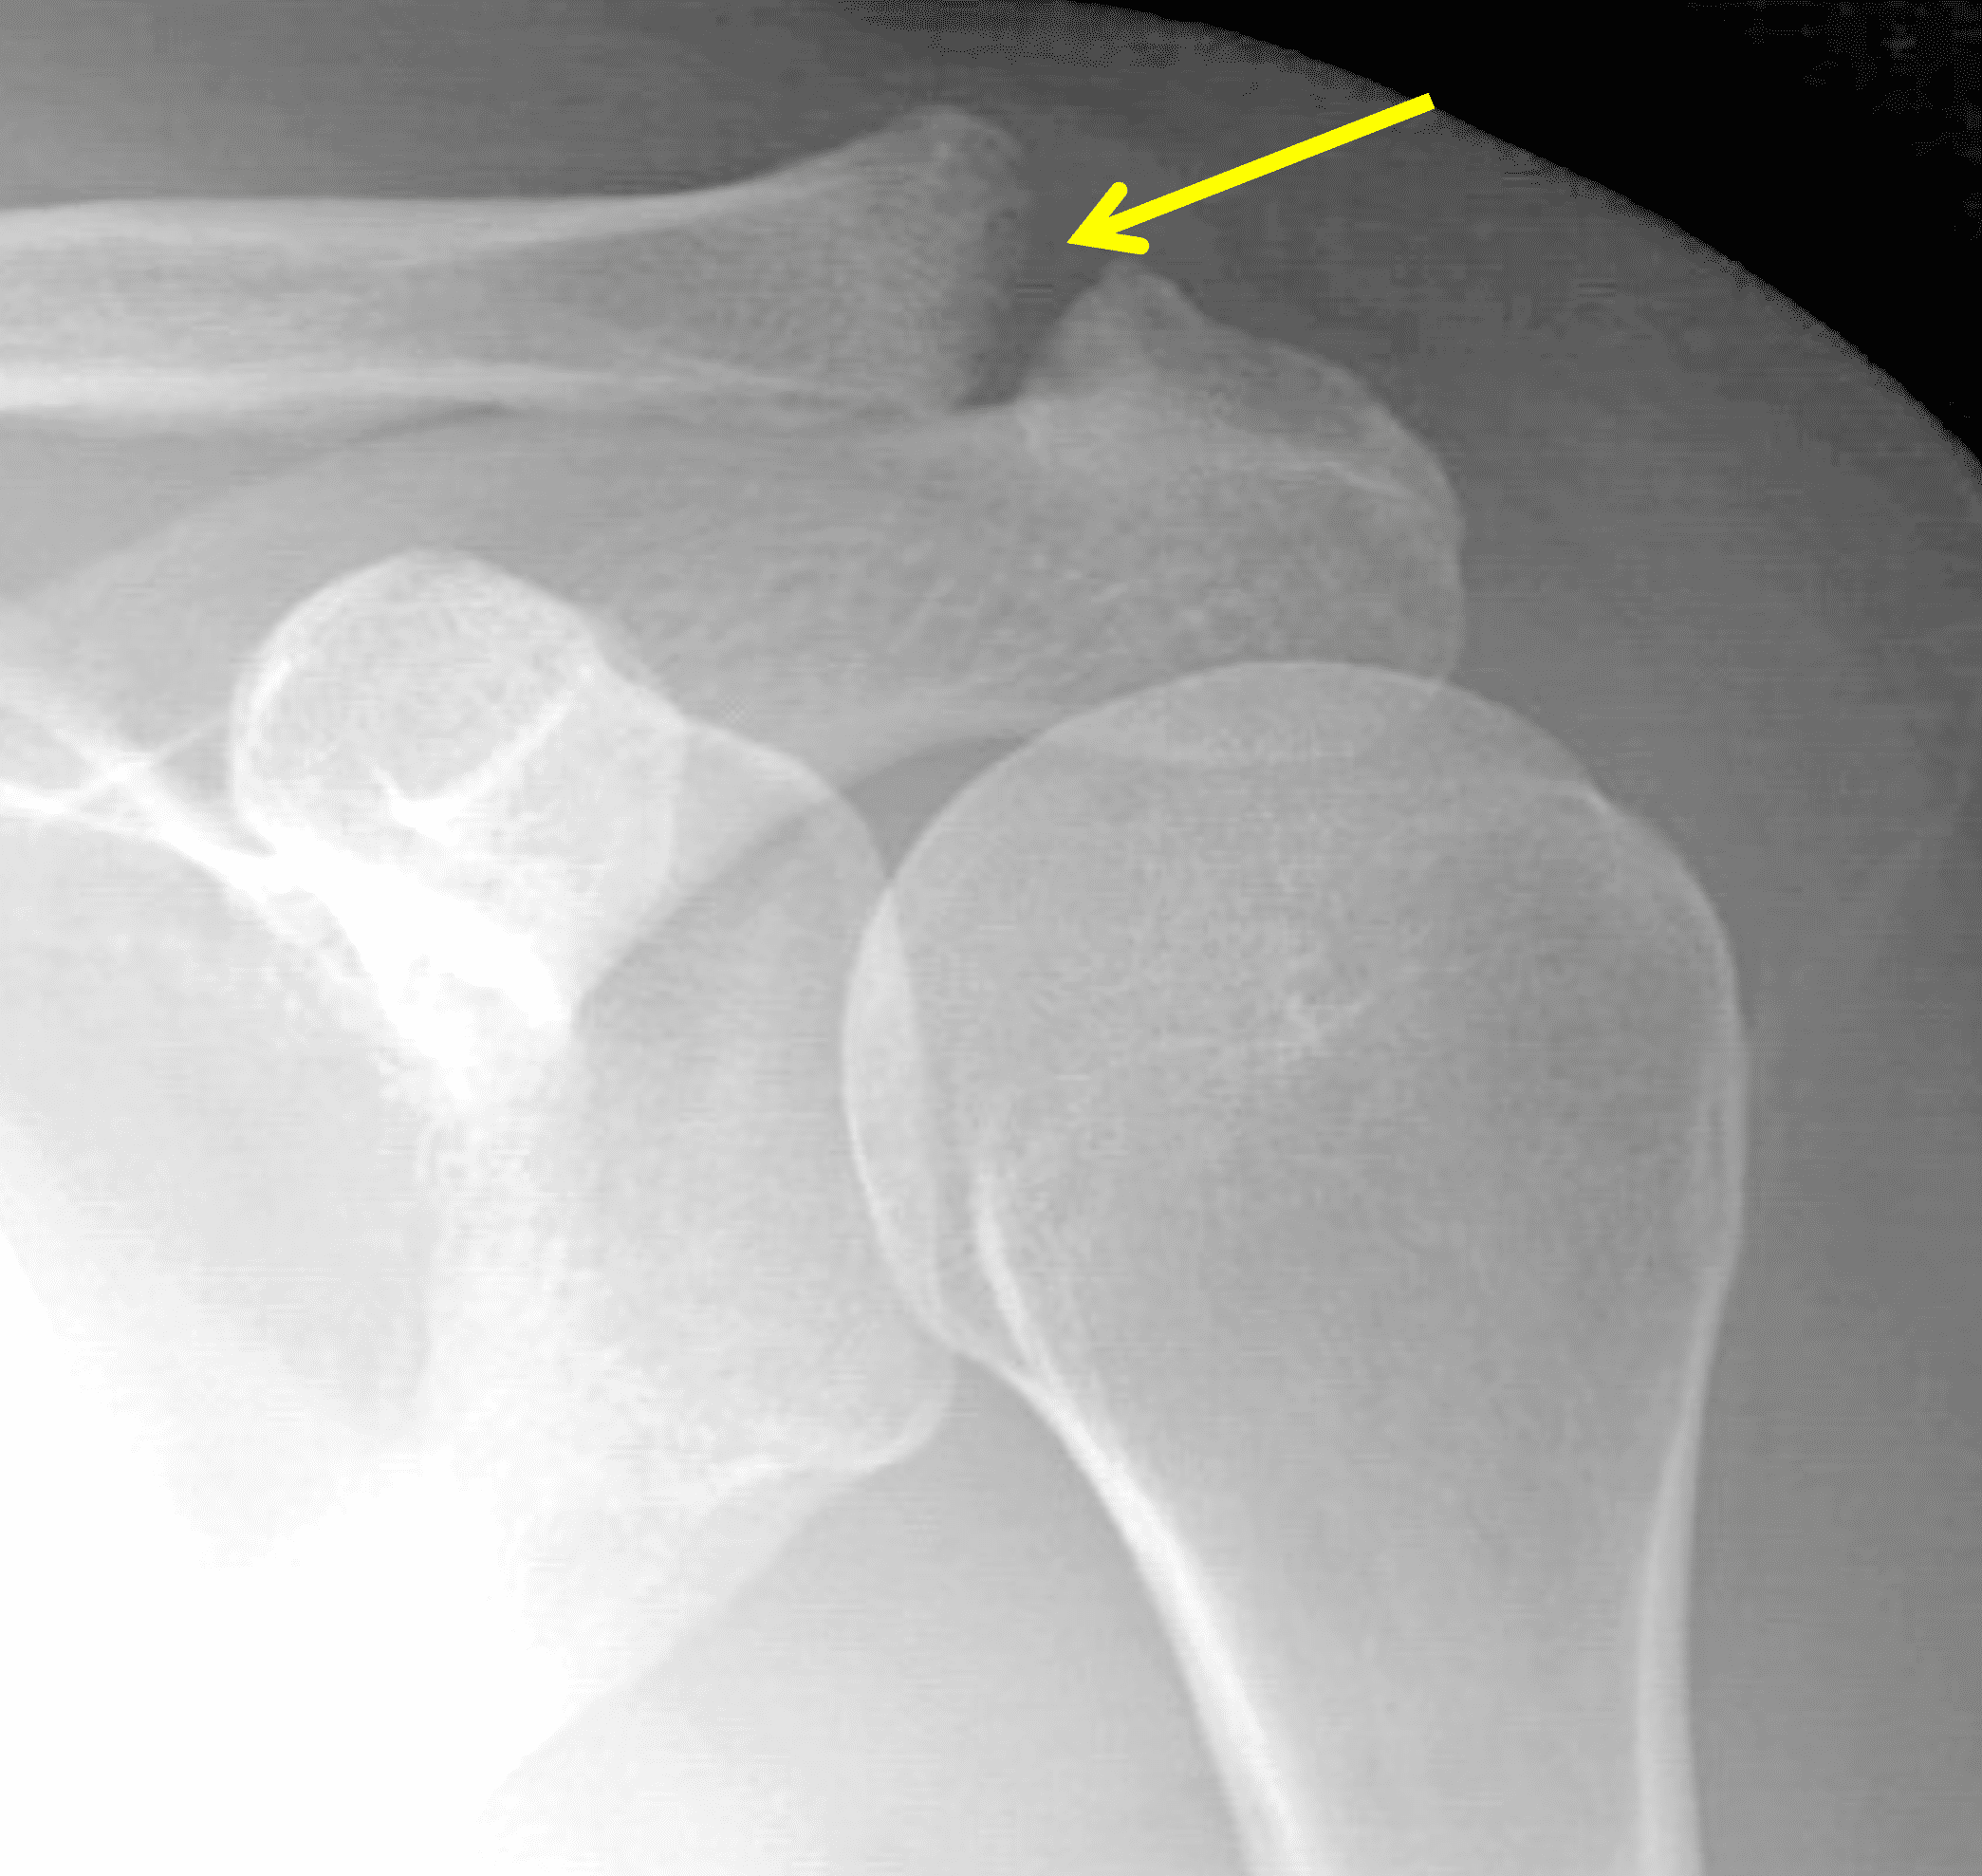

A 49-year-old male, avid weightlifter complains of chronic pain along the superior aspect of his right shoulder. He denies acute trauma. An AP radiograph (Figure 1A), as well as oblique coronal SPAIR (Figure 1B), axial fat-suppressed fluid sensitive (Figure 1C), and oblique sagittal T2-weighted images (Figure 1D) are shown. What are the findings? What is your diagnosis?

Radiographs: Initial radiographs may be normal or show features of other common unrelated AC joint pathology such as osteoarthritis. As inflammation and hyperemia in the distal clavicle progresses, bone density in the distal clavicle can decrease with indistinctness or discontinuity of the subchondral bone plate (Figure 3).  This so-called resorptive phase may also include frank erosions in the distal clavicle or a faint sclerotic line in the medullary space of the distal clavicle parallel to the bone end. Varying degrees of surrounding soft tissue swelling may be visible.  Later, during the late healing phase when symptoms have usually resolved, the distal clavicle may return to a normal radiographic appearance; a sclerotic line parallel to the distal bone end is visible after healing in some cases (Figure 4).  In patients with severe initial bone loss, re-cortication of the resorbed bone and erosions can occur leaving residual bone loss and contour defects in the distal clavicle. While it is typically not a primary modality for the diagnosis of DCO, CT demonstrates the same bone findings as radiographs.